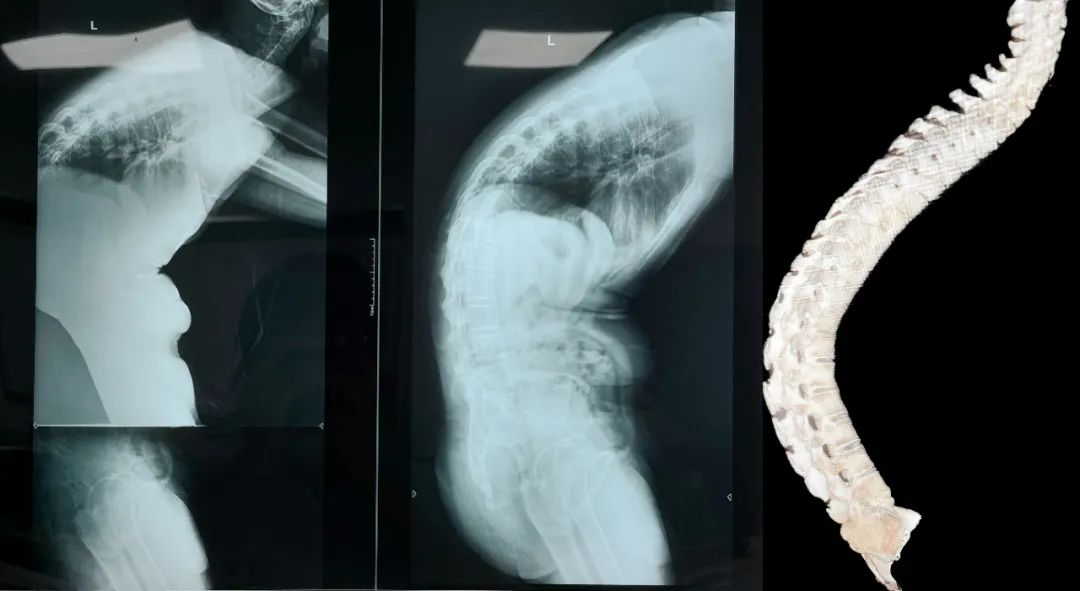

术前:术前正侧位,脊柱后凸Cobb角70°

不久前,骨科陈子华主任接诊了一位33岁特殊的患者,年纪轻轻,病情却不容乐观。丘先生的脊柱畸形十分严重,身体弯曲到接近“折叠”的状态,从他的身后看过去,只能看到高高隆起的后背。17年前患者曾确诊为强直性脊柱炎,被冠为“不死癌症”。约10年前开始,患者出现胸腰背部僵硬,逐渐出现胸腰背部后凸畸形,近2年症状加重明显,原本直直的脊柱,硬生生弯成了“弓”,站立时的体态如同鞠躬,睡觉无法平躺,只可侧躺,严重影响生活质量。

入院后完善相关检查,查体见患者整体脊柱后凸畸形,颈椎及髋关节活动度尚可。在陈子华主任的带领下,朱立新教授指导下,经过全科查房讨论,脊柱外科团队制定周密的术前规划,综合考虑患者的直立、平视、端坐、平躺等功能,设计截骨位置并计算截骨角度,制定个性化治疗方案:强直性脊柱炎胸腰椎后凸畸形、腰2/3、腰1/2、腰1/胸12、胸11/12截骨矫形术+椎管扩大成形+神经根管减压+钉棒系统内固定术。